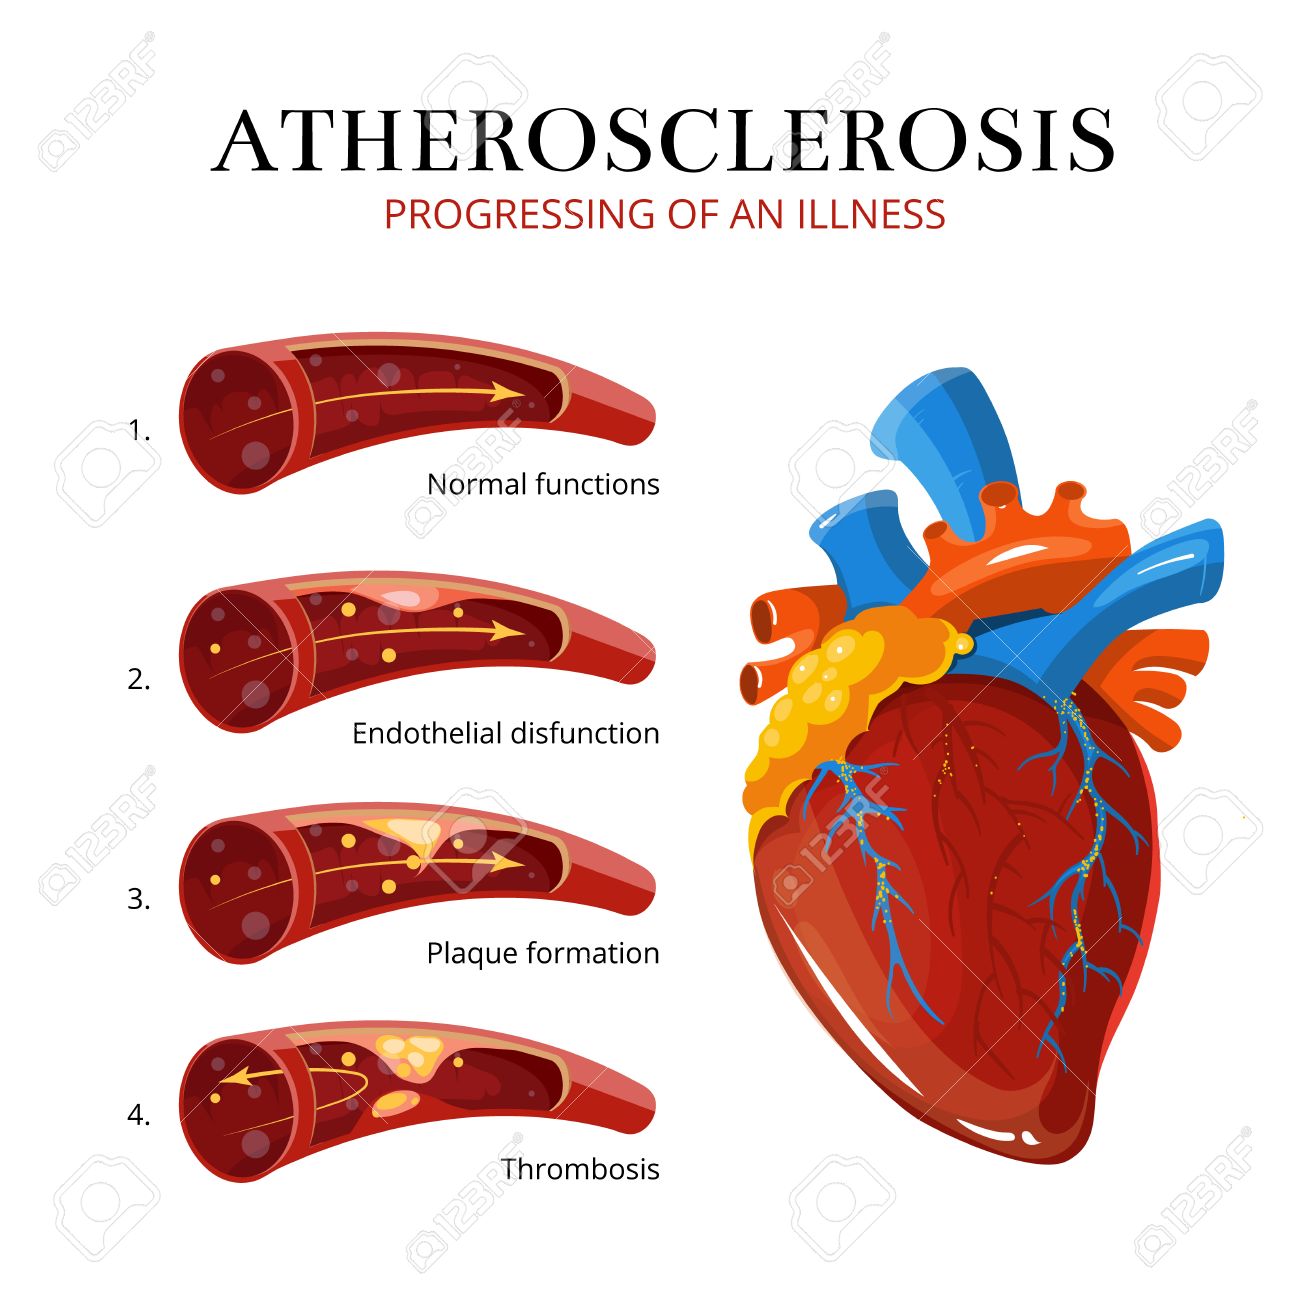

血栓症 イラスト (337 無料写真)

血栓症」のイラスト素材・ベクター画像 - イメージマートimagemart。

血栓症」のイラスト素材・ベクター画像 - イメージマートimagemart。

血栓塞栓症」の1063点のロイヤリティフリー画像、写真素材、絵Shutterstock。

動脈血栓症の図は 心臓発作を開発する血の塊です 原因と健康上の問題の危険因子 ストックベクター ©solar22 185087722。

アテローム血栓性脳梗塞のイラスト イラスト素材6874946- フォトライブラリ。

血栓症」のイラスト素材・ベクター画像 - イメージマートimagemart。

血栓症」のイラスト素材・ベクター画像 - イメージマートimagemart。

動脈硬化、血栓形成。ベクトル医療イラスト。内部の臓器、血栓症、血管内皮のイラスト素材・ベクター Image 61855962。